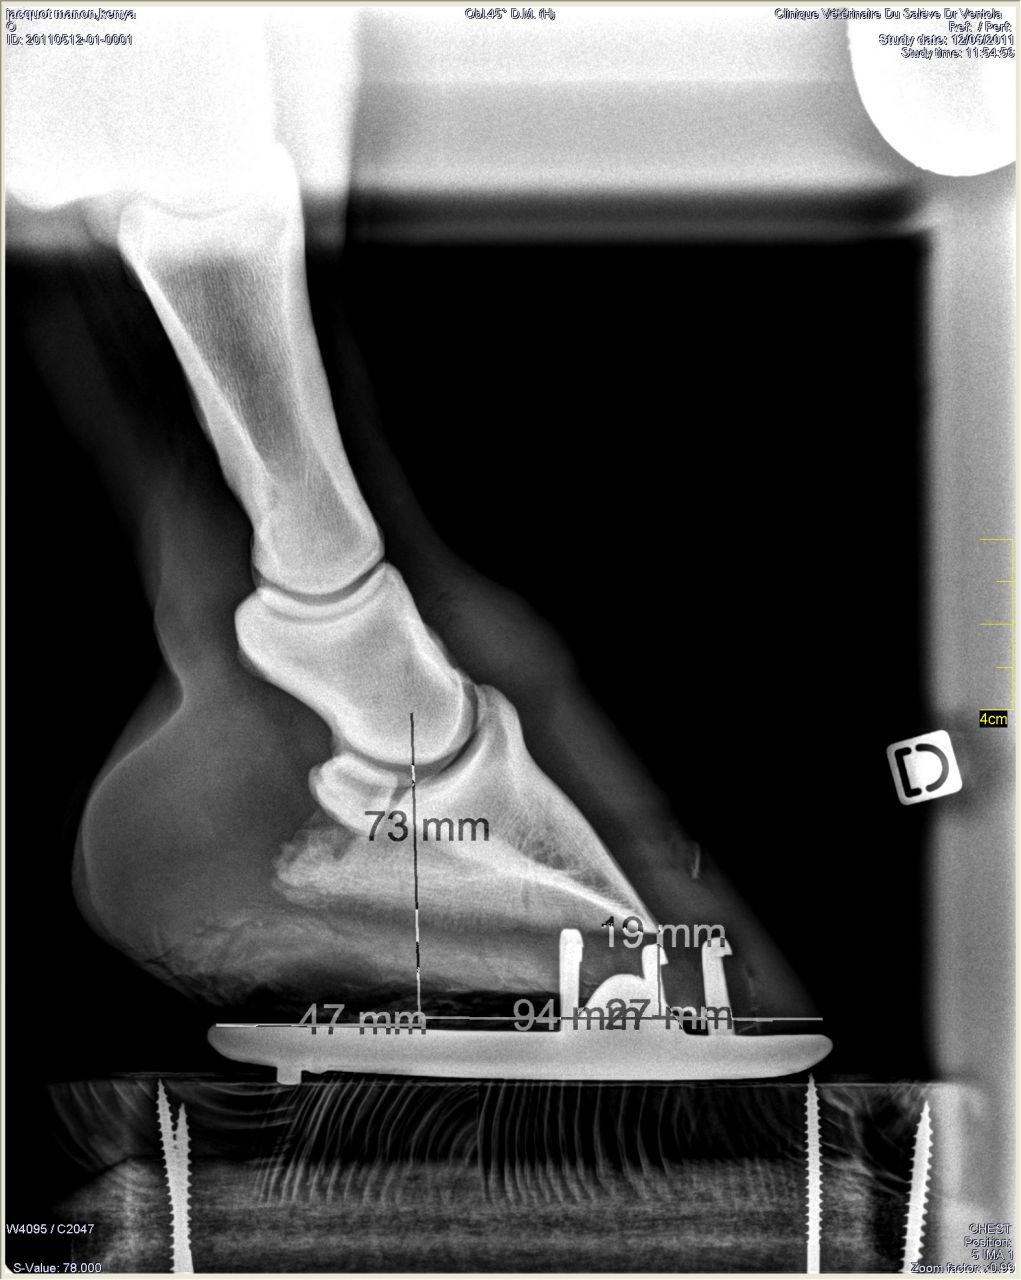

| Dire merci | Antérieur droit de profil: RAS à part le même problème de répartition du pied![]() De face à plat: ![]() De face en extension: ![]() |